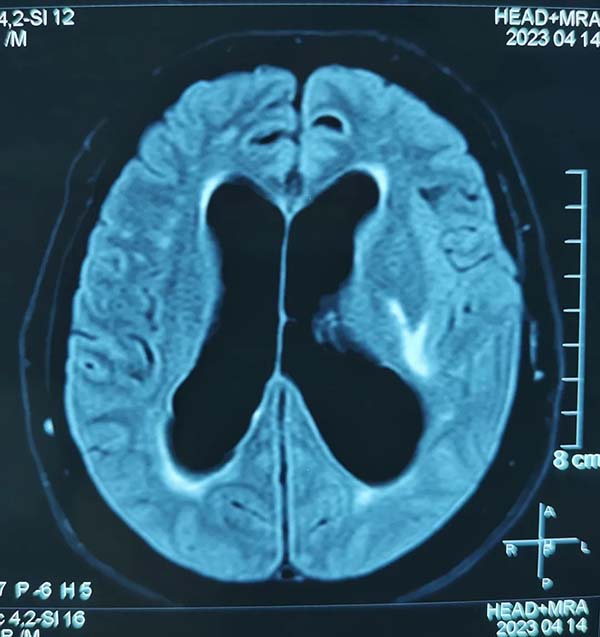

患者,女性,61岁,2019年底于北京某医院行颅脑肿瘤手术,术后曾在我院行放射治疗。近3个月以来,患者出现双下肢无力,走路不稳,生活不能自理的问题。经多方咨询,到我院神经外科就诊。冯富强主任组织全科人员进行详细术前讨论,认为患者颅底残留肿瘤再次切除风险高,获益小,目前主要症状为交通性脑积水所致,本次手术应以改善患者症状,提高生活质量为主,遂在全麻下行腰大池腹腔分流术。手术过程顺利,术后患者恢复良好,目前已正常行走。

腰大池腹腔分流术治疗脑积水,较其他脑脊液分流手术具有以下优势:手术操作简便、安全;安全脑组织外操作,减少了皮质损伤、脑室出血等并发症;手术路径短,手术时间相应也较短,减少了麻醉和术中感染的风险;无脑室端梗阻风险;不影响脑室系统脑脊液生理循环。

本例手术是我院首例腰大池腹腔分流术,是我院神经外科的又一项新技术突破。脑转移及脑膜转移导致的梗阻性脑积水,诊断“脑梗塞、脑动脉硬化”在内科行保守治疗的常压性脑积水,神经外科都可以积极干预,改善患者症状。我们需要普及脑积水治疗理念,及时更新脑积水治疗术式,为医院的发展贡献力量,为患者提供更优质的医疗服务。